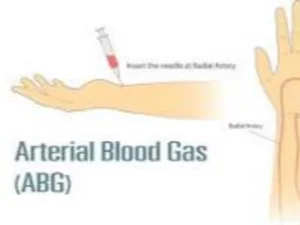

2. Arterial Blood Gas

- A blood sample taken from an artery to determine acid base balance

Luanne ABG comes back, what state is she in: pH 7.33, PC02 47, HCO3 30.

1. Respiratory acidosis partially compensated

2. Metabolic acidosis uncompensated

3. Metabolic alkalosis partially compensated

4. Respiratory acidosis compensated